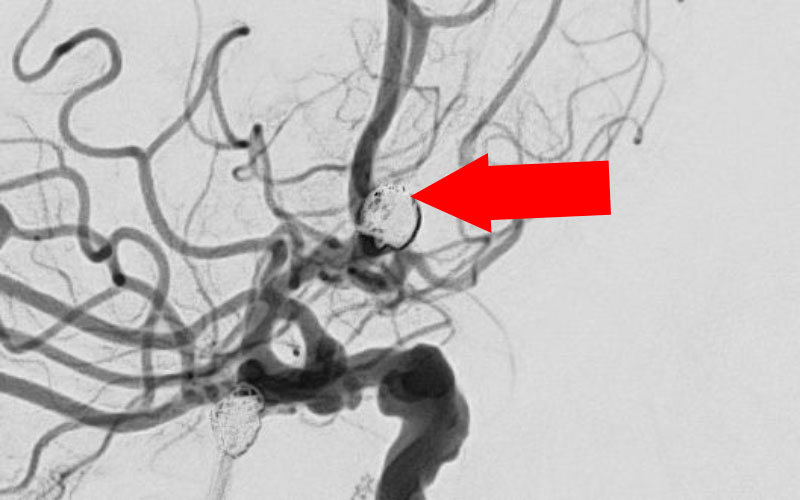

脳動脈瘤(血管内治療)実績一覧 (合計 791 件)

※ 画像をクリックすると拡大表示します。症例No.をクリックすると詳細ページを表示します。